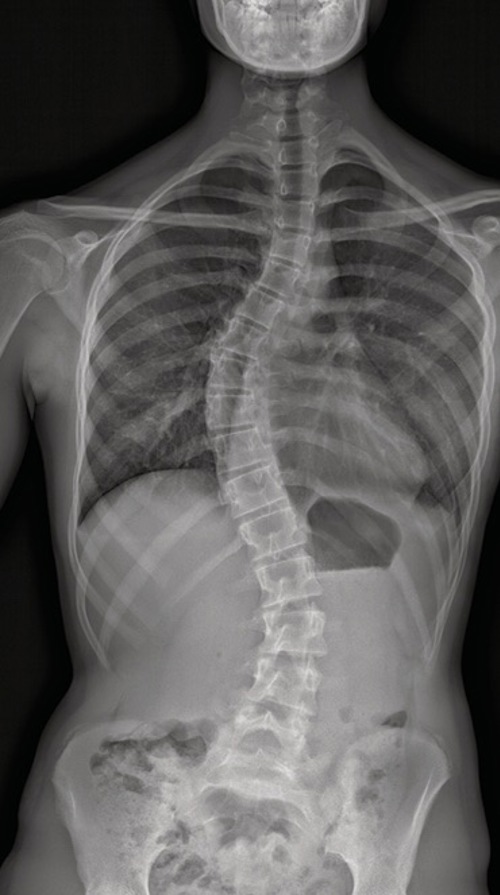

Etwa zwei Prozent aller Jugendlichen entwickeln eine adoleszente idiopathische Skoliose – eine Wirbelsäulenverkrümmung, die zwischen dem 10. und 18. Lebensjahr auftritt (adoleszent) und deren Ursache wissenschaftlich ungeklärt ist (idiopathisch). Glücklicherweise ist sie bei drei Vierteln nur leicht und lediglich bei fünf Prozent davon stark ausgeprägt. Mädchen sind viermal häufiger betroffen als Jungs.

- Einseitiger Schulterhochstand

- Einseitiges Vorstehen der Rippen

- Beckenschiefstand

- Asymmetrie des Rückens